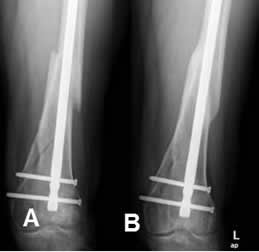

Fig 88. Consolidación radiológica.

A: Rx AP. Fractura de la diáfisis femoral, estabilizada con clavo de Kuntcher.

B: Rx AP después de 18 meses. Adecuada consolidación, con formación de callo óseo compacto.